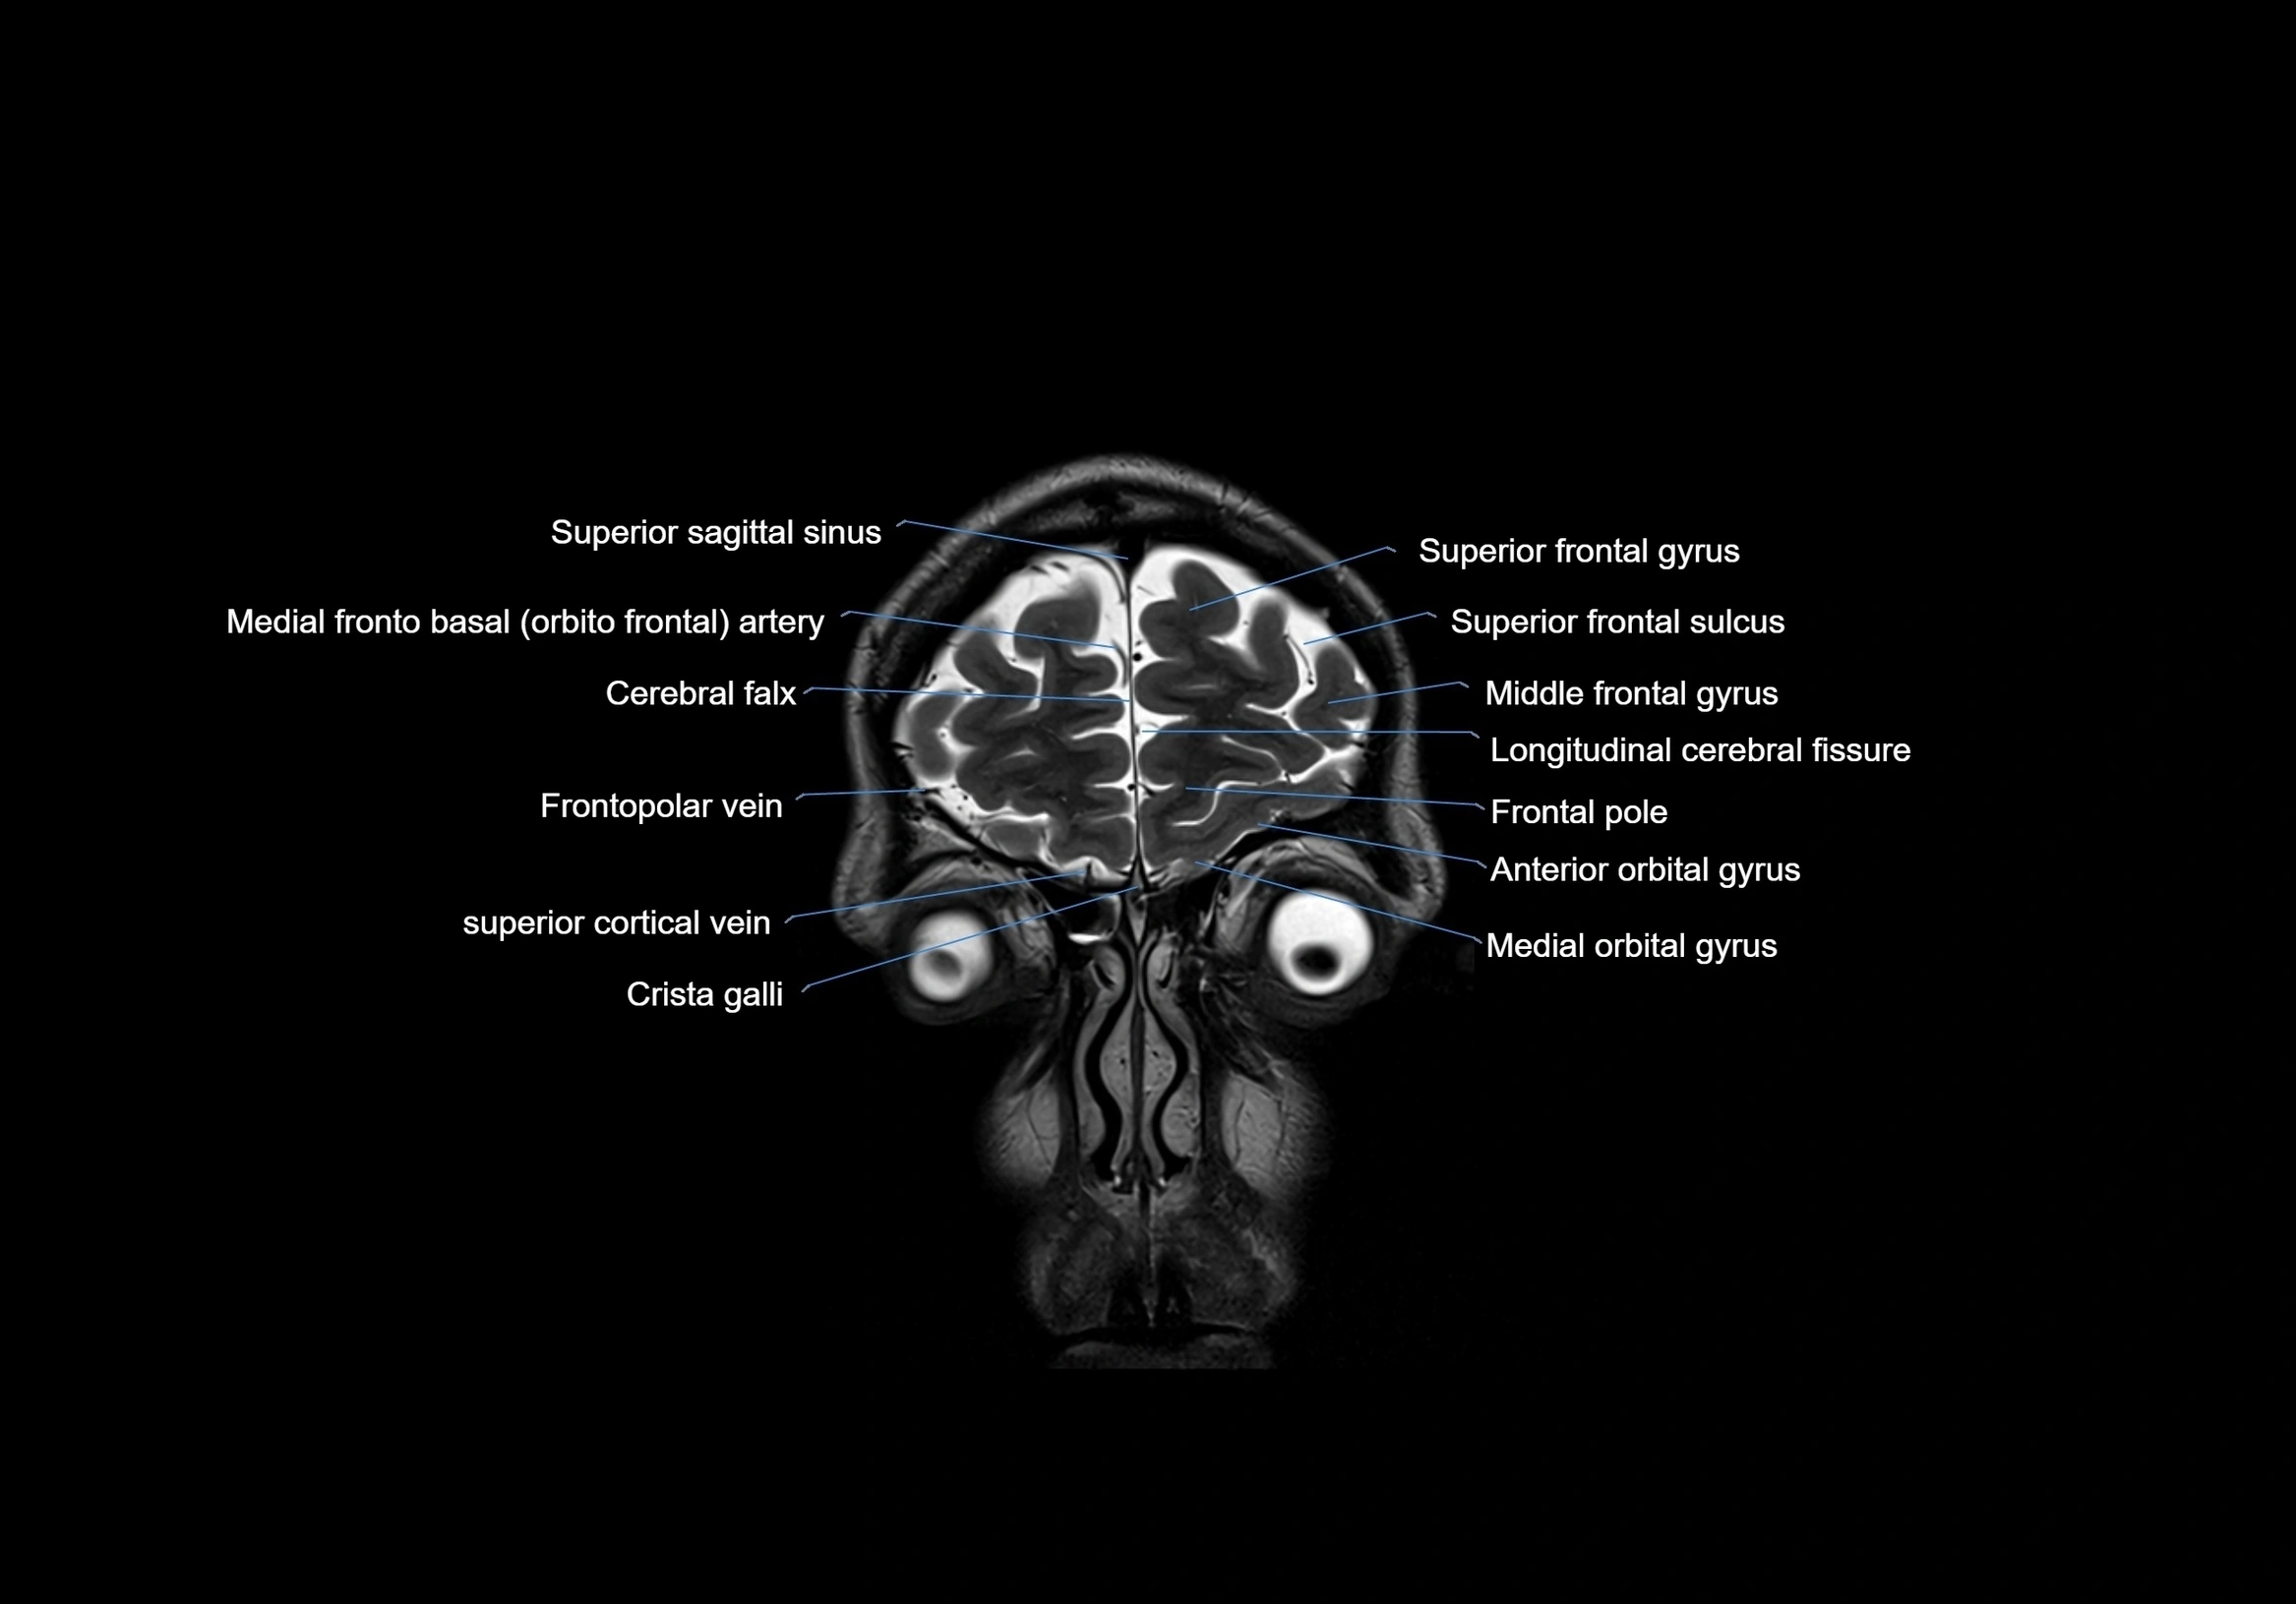

MRI images